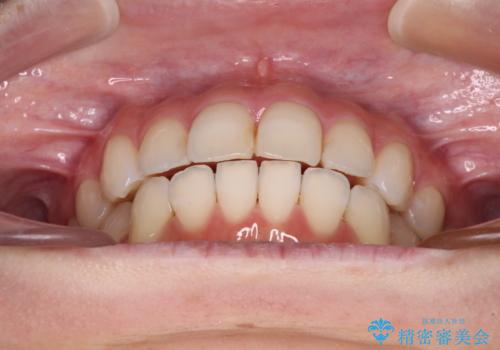

- 前歯のデコボコを気にして来院された患者様です。

主に下顎歯列全体の後方移動とIPR(歯と歯の間を削る)によってデコボコが解消するように設計し、インビザラインにより治療を行うこととしました。

舌突出癖がある方ですと、叢生が解消すると同時に前方に拡大されてしまいますが、ゴムかけをしっかりと行ってくださったこともあり、スッキリとした仕上がりとなりました。